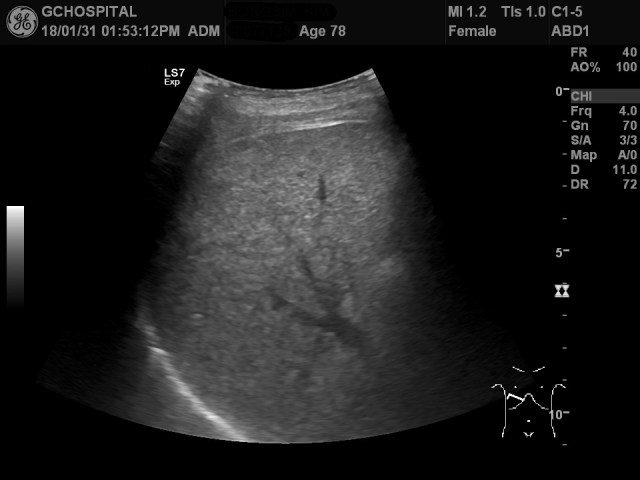

간의 지붕부위를 좀 더 관찰하기 위해 엎드리게 한 상태에서 얻은게 위의 두 영상입니다. 앞서 누워있는 상태에서도 간의 지붕부위를 거의 다 확인할 수 있었지만, 엎드려서 얻은 영상이 확실히 더 깔끔하게 횡격막윤곽 전체를 포함해서 간의 지붕부위를 보여주고 있습니다.

이렇게 고령의 환자분들의 경우에는 젊고 건장한 환자들보다 더 많은 시간과 노력을 들여서 검사해야만 간의 지붕부위를 비롯한 간담도계의 장기들을 확인하는게 가능합니다. 결국, 조금 더 집요하게 확인이 안된 부위가 있었는지 체크하고 다양한 시도를 할 때에만 충분히 확인해봤다고 자부할 수 있는 검사가 가능한 것입니다. 수학에는 왕도가 없다는 말처럼, 초음파 영상진단에도 왕도가 없다는 것을 새삼 느끼게 해주었던 사례였습니다.